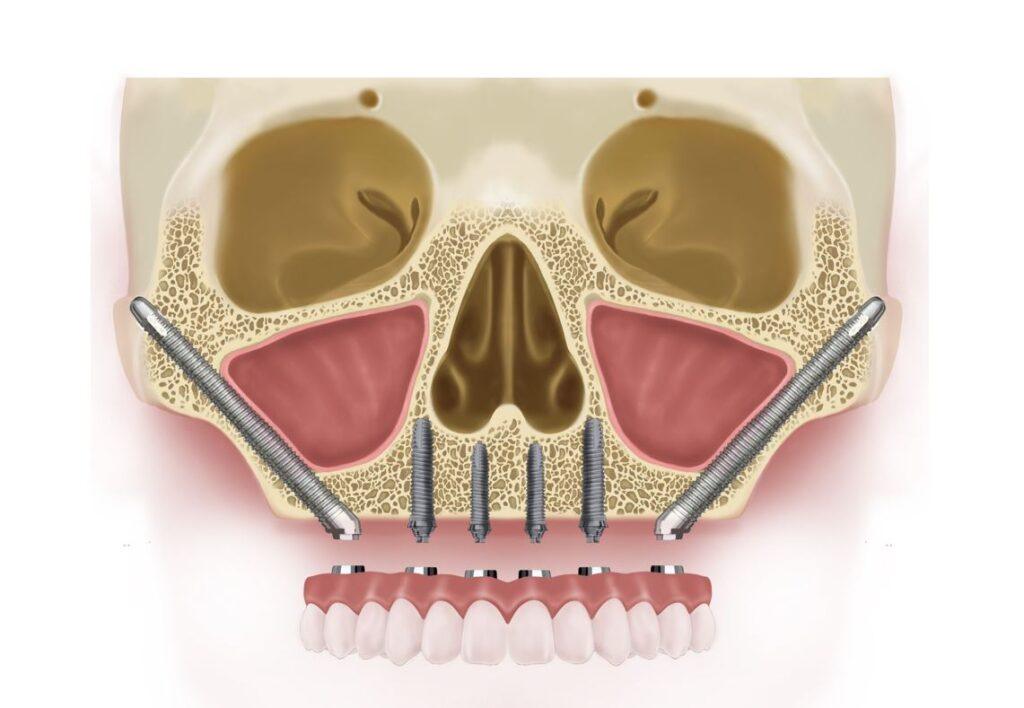

五、顴骨植牙(Zygoma Implant)

技術原理

當上顎骨流失嚴重,利用顴骨(顴弓)打入特殊長型植體。

適合對象

- 嚴重骨缺損者

- 多次植牙失敗者

- 年輕但骨量不足者

優點

- 無需補骨

- 成功率高(但需高技術)

缺點

- 難度高、醫師技術門檻高

- 台灣能做的醫師少

- 價格昂貴